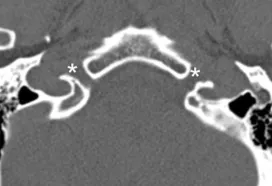

Coronal plane image of cribriform plate (asterisks).

Axial CT of foramen rotundum (asterisks).

Axial CT of superior orbital fissure (arrows) and optic canal (asterisks).

Axial CT of foramen rotundum (asterisks).

Axial CT of foramen ovale (arrows).

Axial CT of facial canal (arrows).

Axial CT of internal auditory meatus (arrows).

Axial CT of jugular foramen (asterisks).

Axial CT of hypoglossal canal (asterisks).